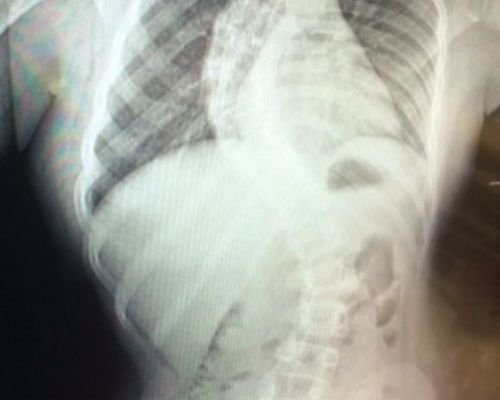

Grace – 10 years on from Spinal Fusion Surgery.

“Today I revisited the hospital where I had my spinal fusion done, and goodness me what an emotional but empowering day it was! To revisit these stairs, which I had to climb up before being sent home, to now running up and down them, made me remember why I am able to live the life I am able to.”

Anna & Autumn – A families take on a scoliosis diagnosis

As a parent I felt really helpless, but I have always trusted all the health professionals who have supported Autumn for the past 8 years”